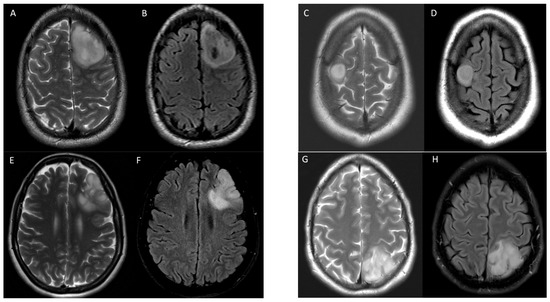

Examples of true positive, true negative, false positive, and false negative results for T2-FLAIR mismatch using consensus reads against 1p/19q co-deletion status are shown in Figure 2.

Figure 2. Examples of T2-FLAIR match and mismatch in 4 patients with IDH1 mutant gliomas with various 1p/19q co-deletion status. Axial T2 (A) and FLAIR (B) images demonstrate T2-FLAIR mismatch in a 25-year-old male with 1p/19q non-co-deletion correctly identified in a true positive instance. Axial T2 (C) and FLAIR (D) images demonstrate T2-FLAIR mismatch in a 58-year-old female with 1p/19q co-deletion in a false positive instance. Axial T2 (E) and FLAIR (F) images show T2-FLAIR match in a 55-year-old male with 1p/19q non-co-deletion in a false negative instance. Axial T2 (G) and FLAIR (H) images show T2-FLAIR match in a 60-year-old female with 1p/19q non-co-deletion correctly identified in a true negative instance. All cases were correctly identified by radiomic model.